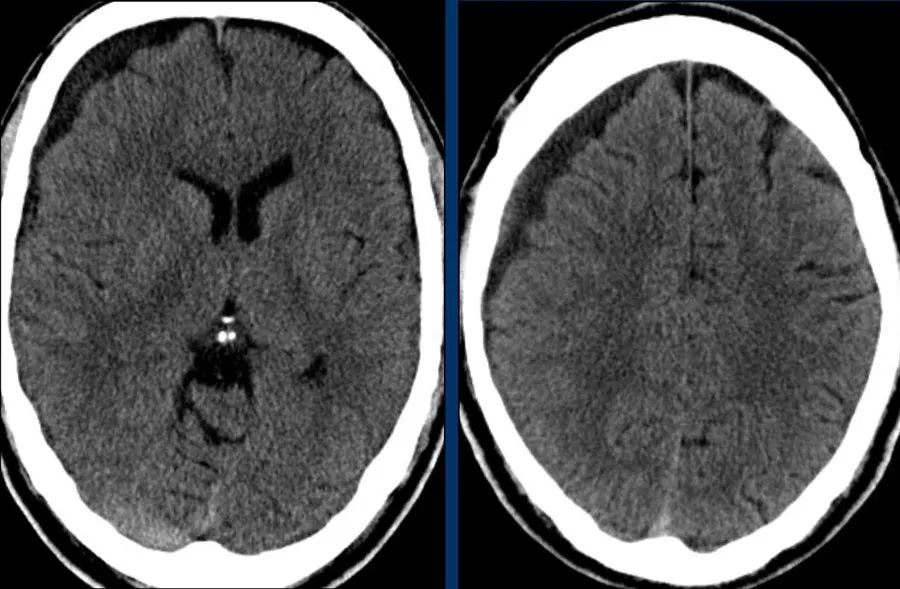

下图显示硬膜下血肿。

注意血肿有高密度区和等密度区。

这可以在超急性出血中看到,但也可以在再出血中看到。

中线结构移位,脑脊液血流受阻,导致右侧脑室颞角扩张(箭头)。

急性硬膜下血肿为高密度(凝血),亚急性血肿为等密度,慢性硬膜下血肿表现为低密度(同脑脊液)。

活动性出血征象:

在急性情况下,硬膜下血肿可能出现异质性:新鲜的非凝血(低)和凝血(高)。